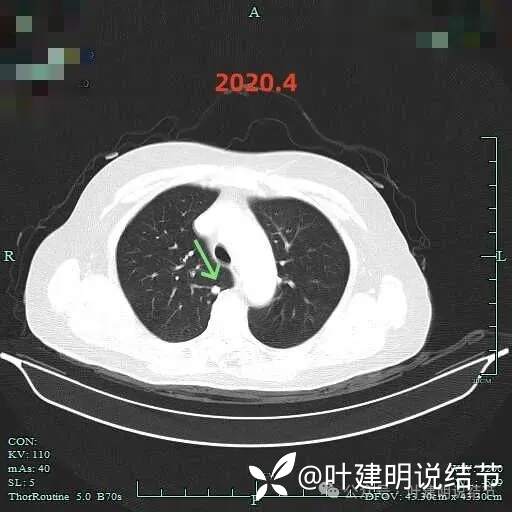

上叶实性结节几乎没有变化。